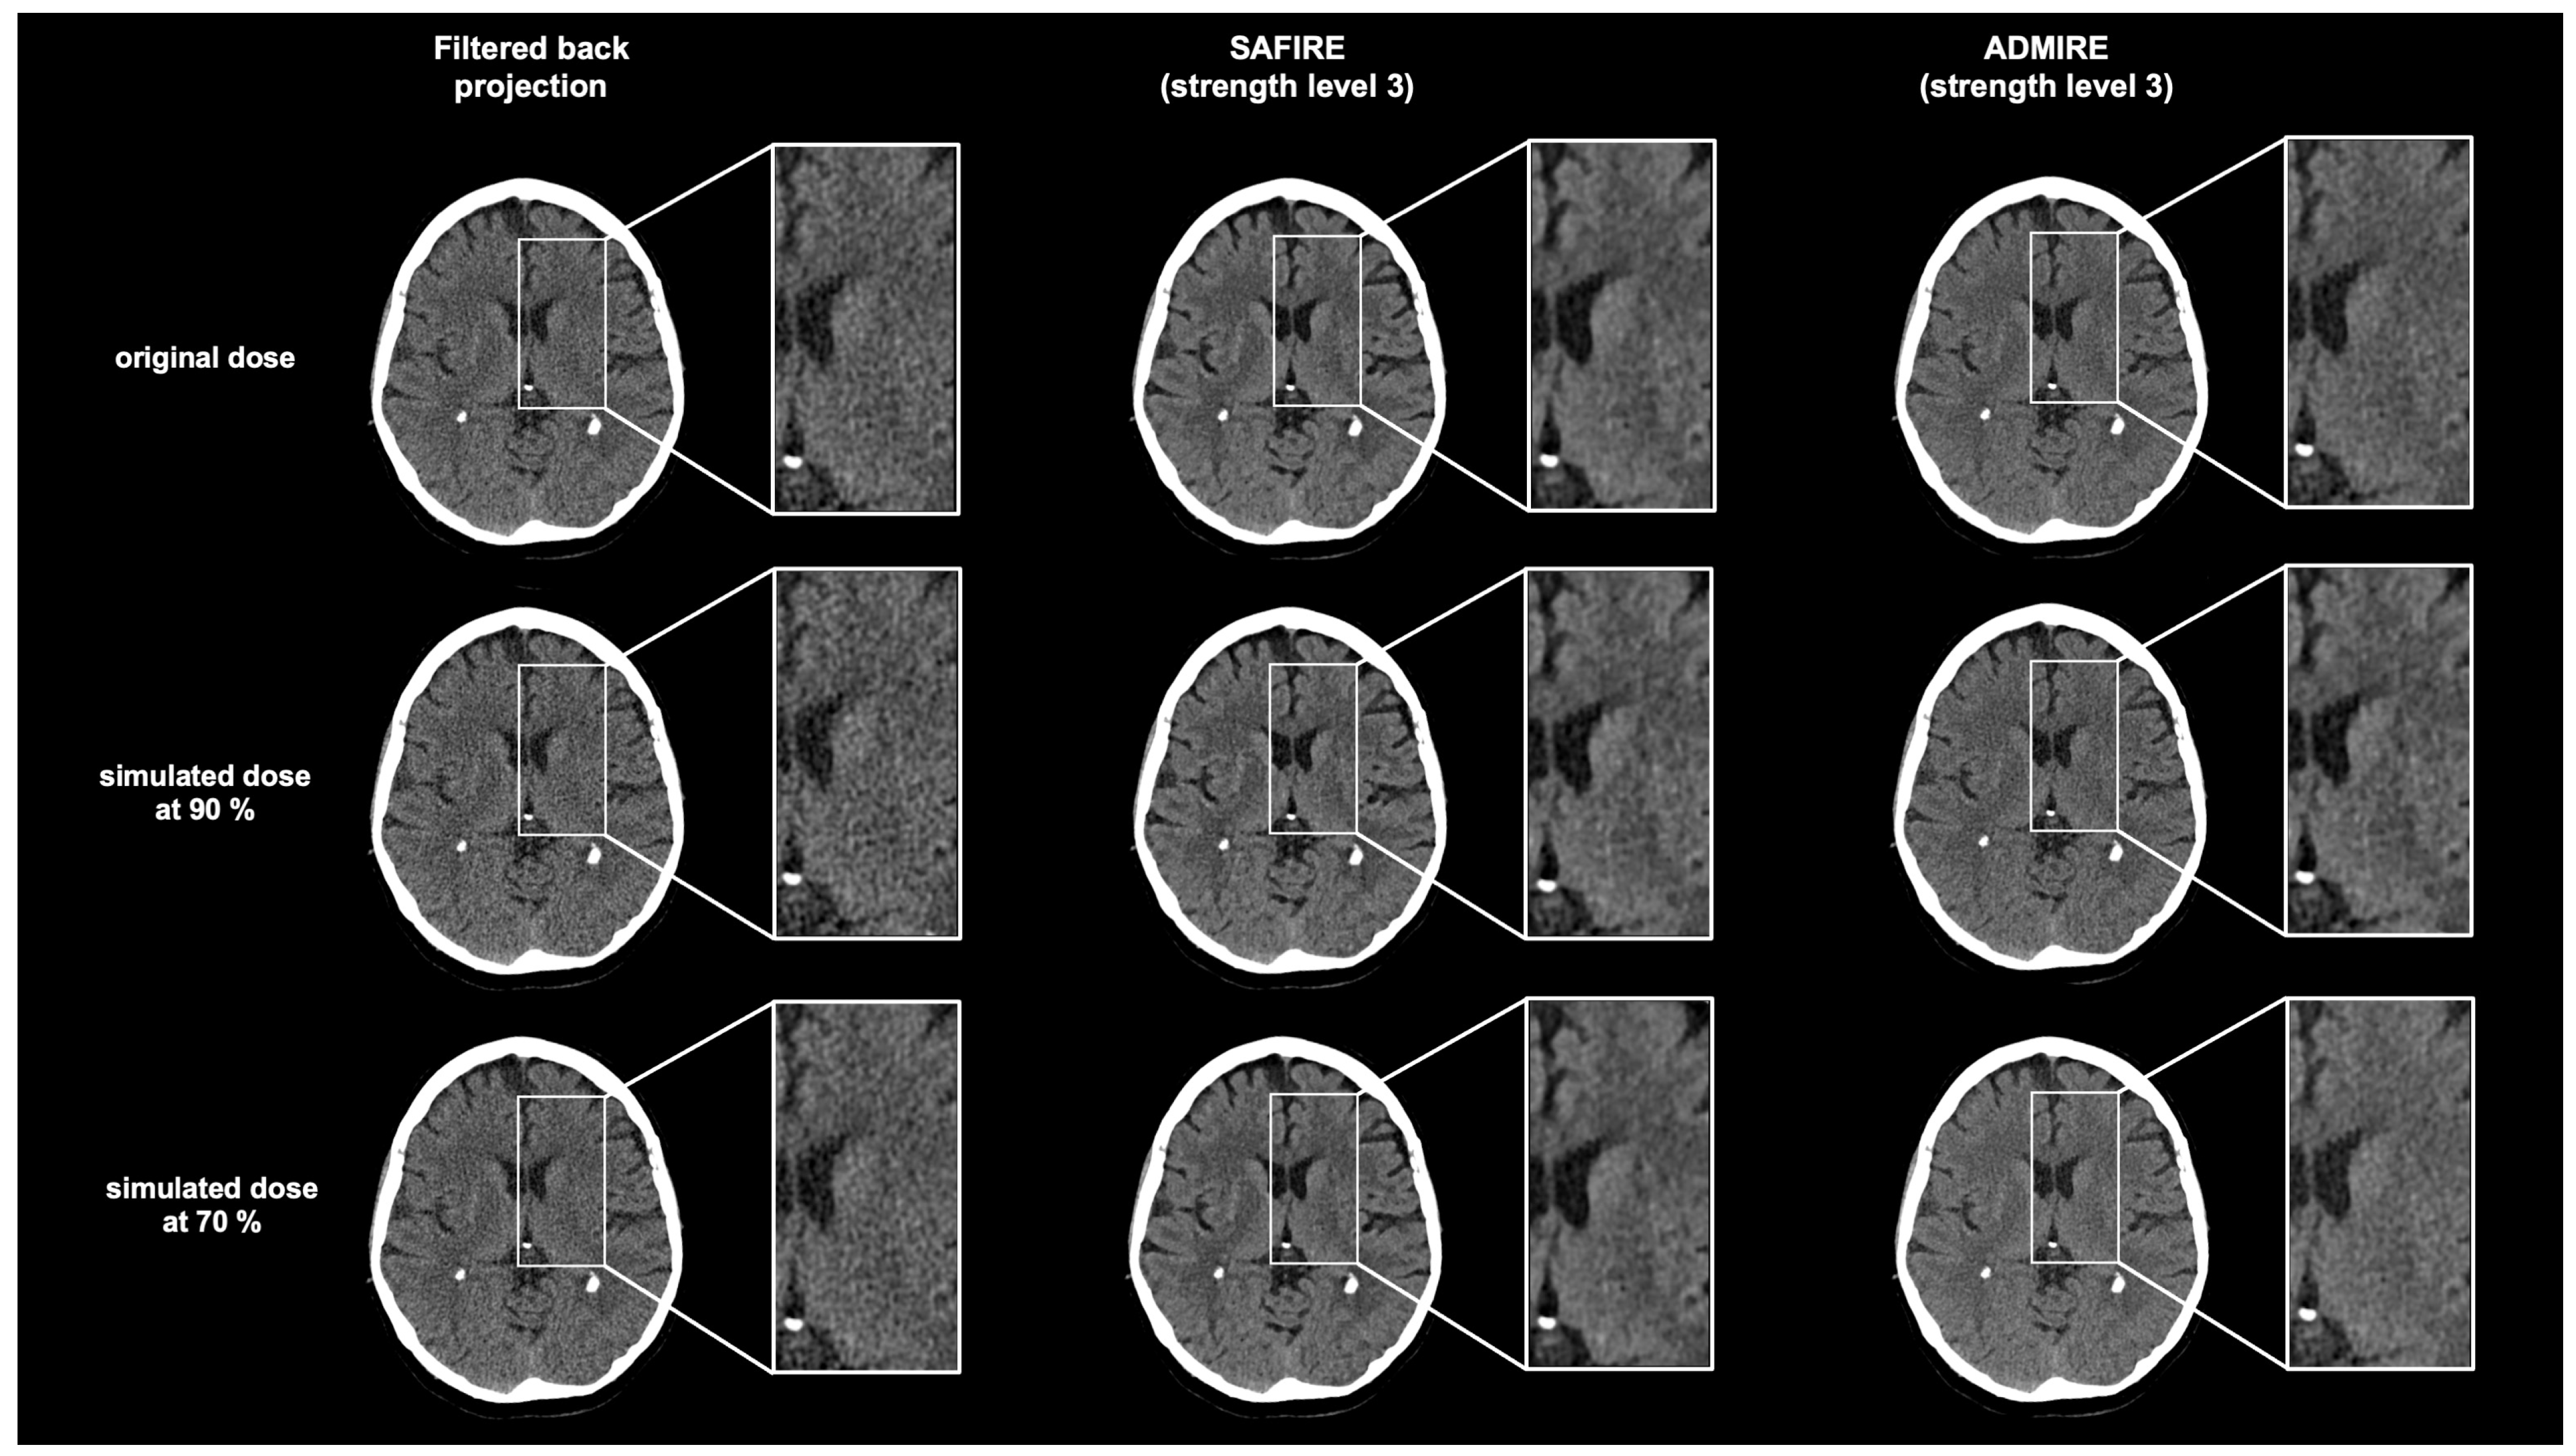

Comparison of ADMIRE, SAFIRE, and Filtered Back Projection in Standard and Low-Dose Non-Enhanced Head CT